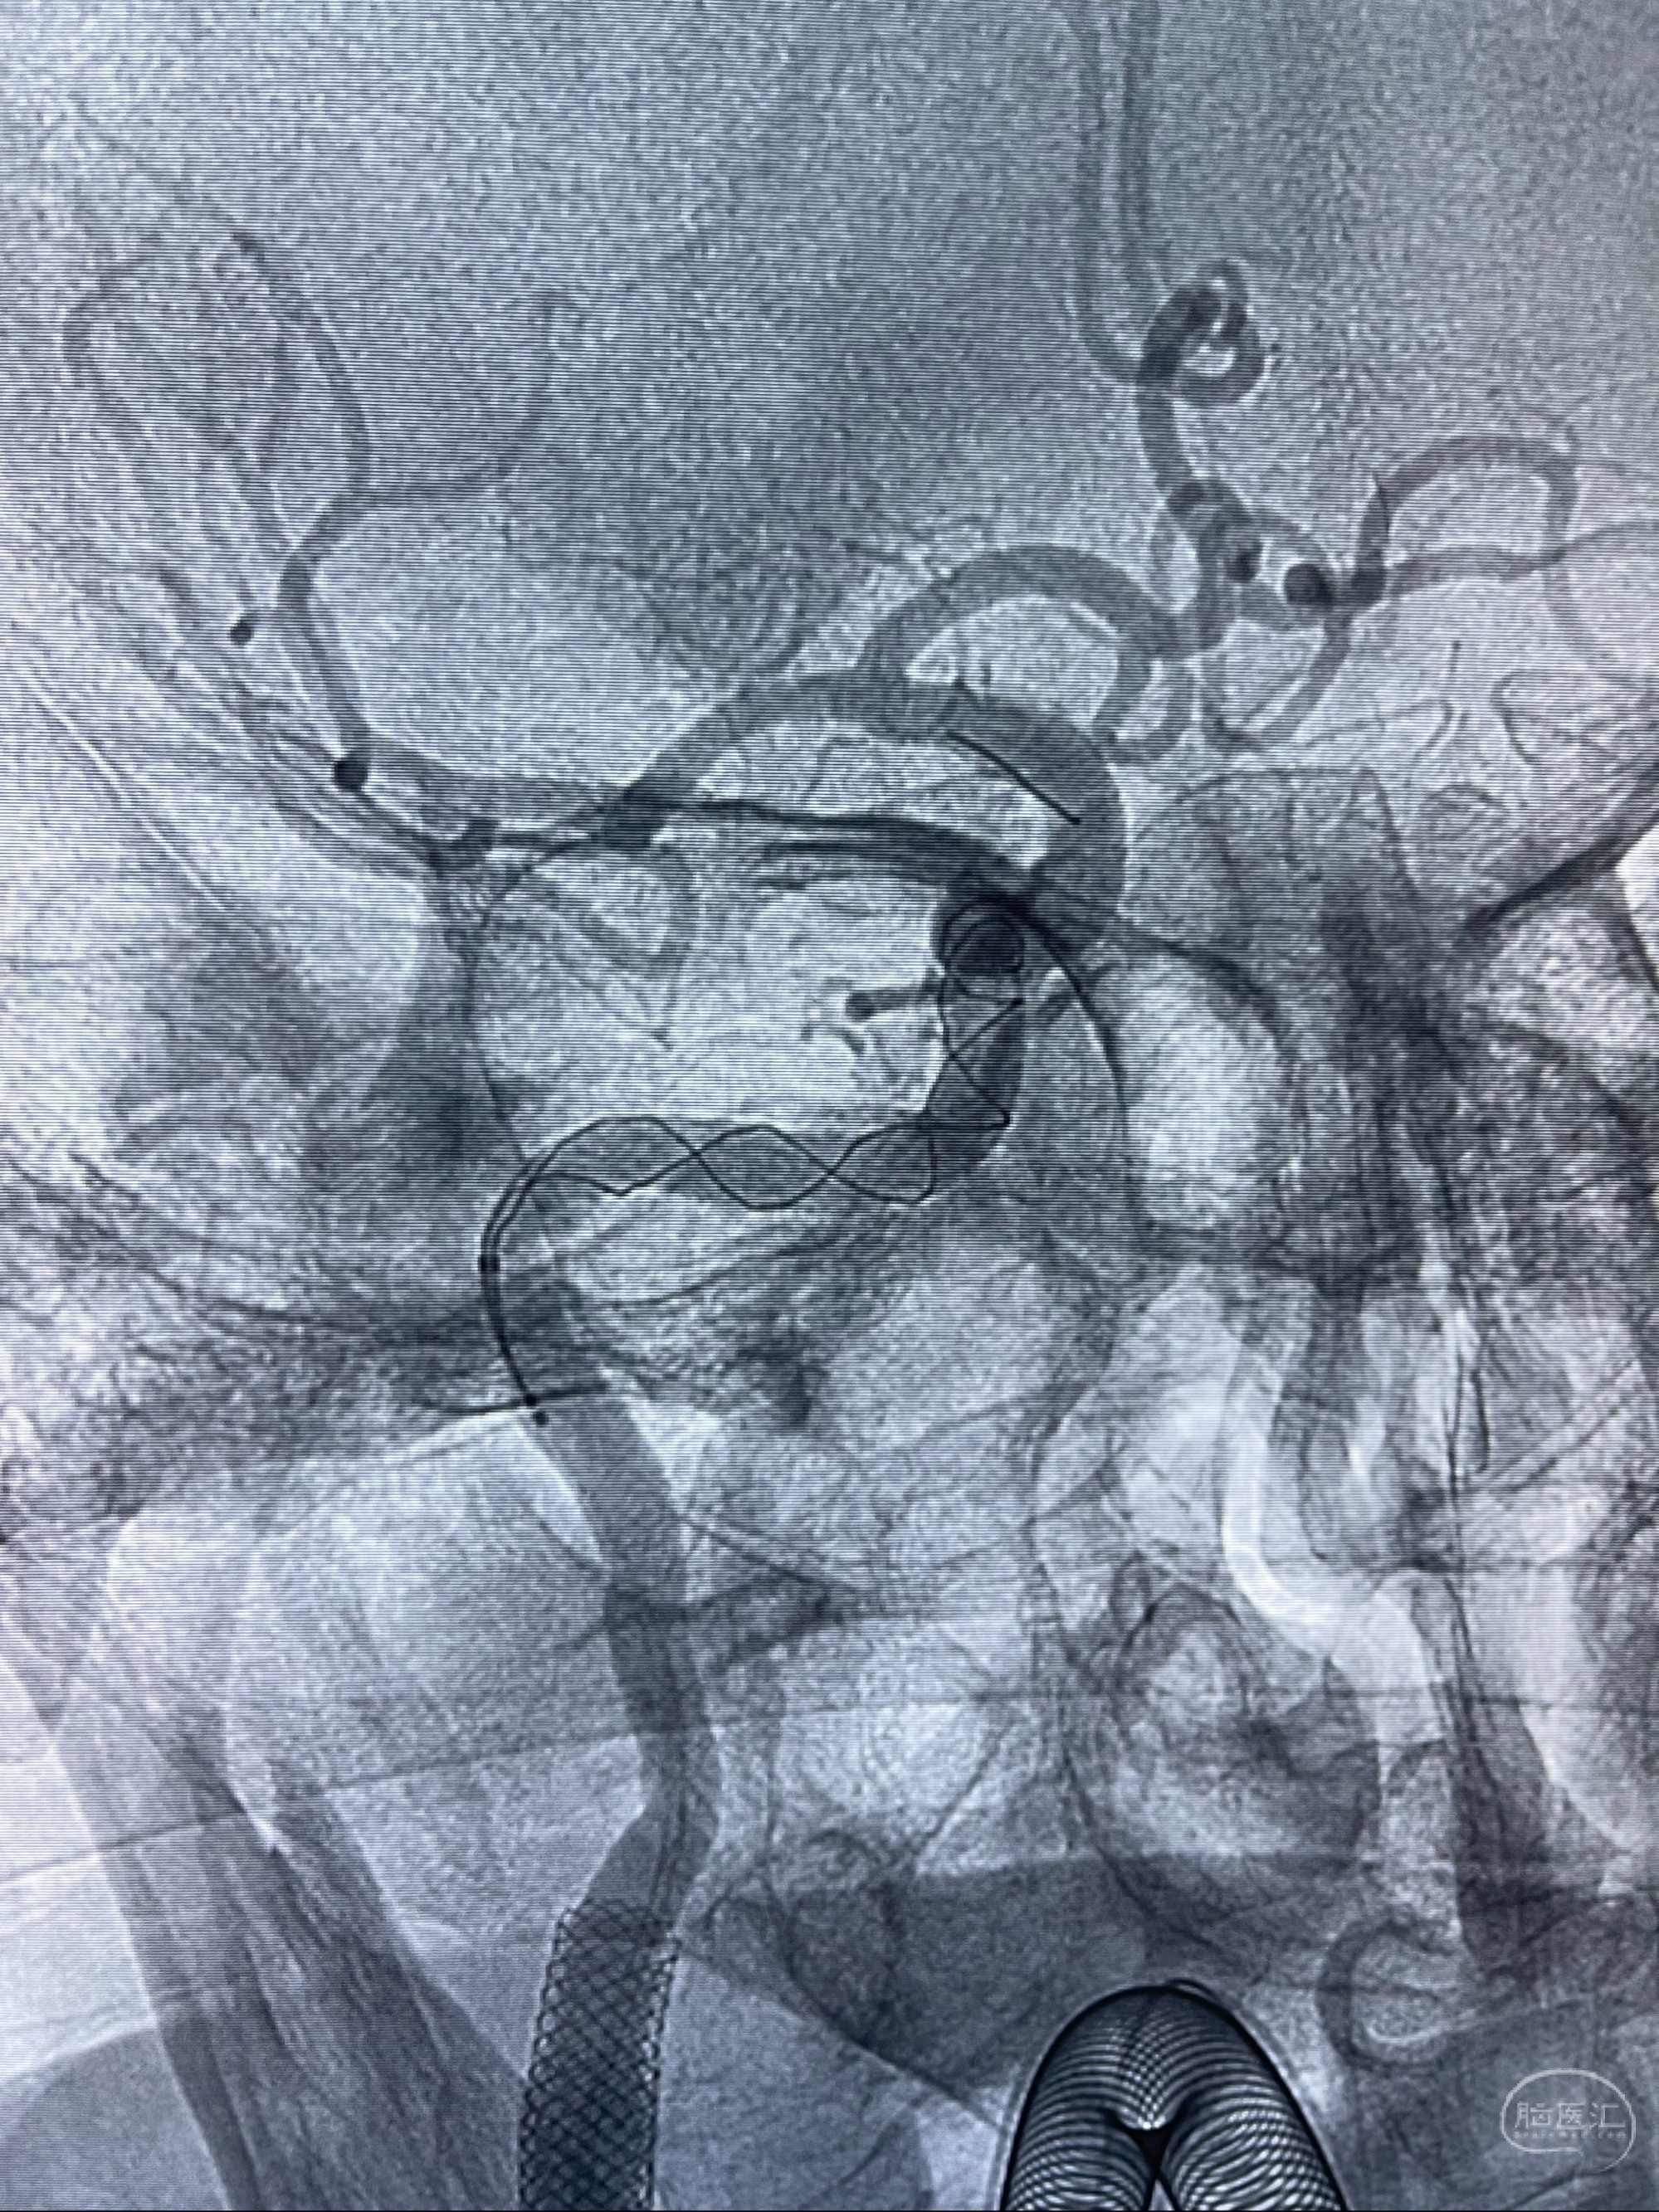

重新行“路径图”,支架导管在微导丝引导下超选择性插入至右侧颈内动脉眼段,4.5-50mmLeo支架释放,远心端位于海绵窦段,近心端位于岩骨段狭窄段以近

即刻造影显示支架贴壁佳

路径图下,5.5-50mmLeo支架导管在微导丝引导下超选择性插入远段Leo支架内

两枚支架部分重叠

多次确认支架位置及打开贴壁情况

支架完全打开,近心端位于原颈动脉支架远心端内

麻醉苏醒佳,遵嘱活动!

术后给予替罗非班300ug/h维持,序贯阿司匹林100mg➕泰嘉75mg口服